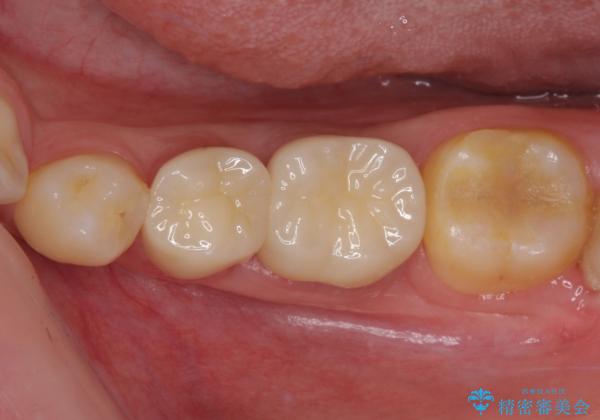

当初は歯肉が腫れ上がり、大変不快な思いをされていましたが、セラミッククラウン装着後は清掃性が著しく改善し、患者様には大変満足していただきました。